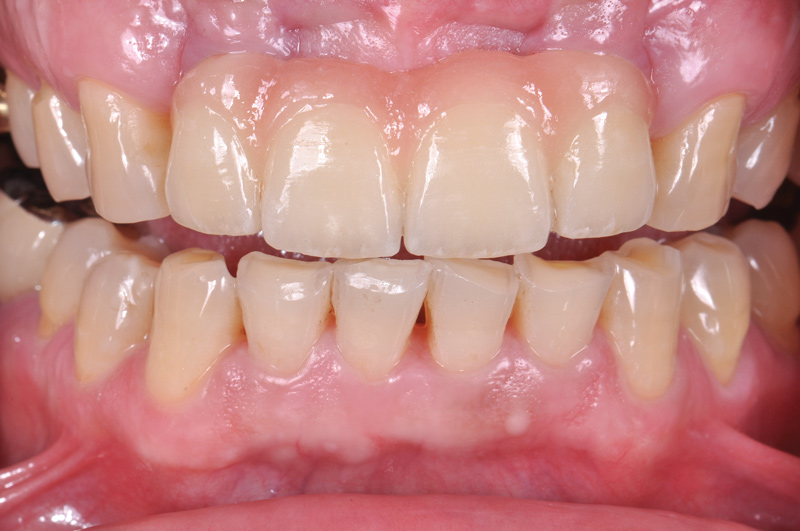

Fig 5. Preoperative view of patient requiring esthetic changes up to at least the bicuspids (Fig 5); postoperative view with CL-I feldspathic porcelain veneers up to the first bicuspid (Fig 6).

Figure 5

Fig 6. Preoperative view of patient requiring esthetic changes up to at least the bicuspids (Fig 5); postoperative view with CL-I feldspathic porcelain veneers up to the first bicuspid (Fig 6).

Figure 6

This class of materials is generally indicated for anterior restorations, but can also be used for the occasional bicuspid and rare molar, providing all parameters are at a very low risk level (Figure 5 and Figure 6).